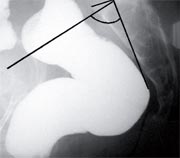

De fait, Michel Prudhomme et coll. ont mesuré, chez 197 patientes, « l’angle d’incidence pelvienne » situé entre la perpendiculaire passant par le centre du plateau de la première vertèbre sacrée et la droite reliant ce centre aux têtes fémorales (Illustration). Ils ont ensuite corrélé cet angle à la descente périnéale évaluée par défécographie.

Ils ont ainsi démontré que cet angle était significativement plus élevé quand le périnée était descendu. En outre, un angle supérieur à 62° était prédictif de périnée descendu avec une sensibilité de 73 % et une spécificité de 82 %.